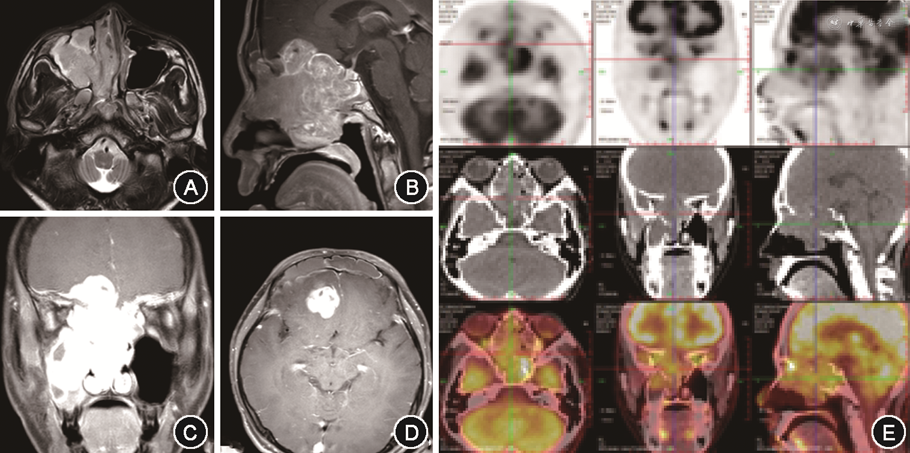

2. 影像学资料:患儿术前均进行CT及MRI检查。MRI通常显示为混杂信号,增强扫描可强化,不均匀,见图1A~1D。正电子发射计算机断层成像(PET/CT)肿瘤表现为代谢增高的软组织影,见图1E。